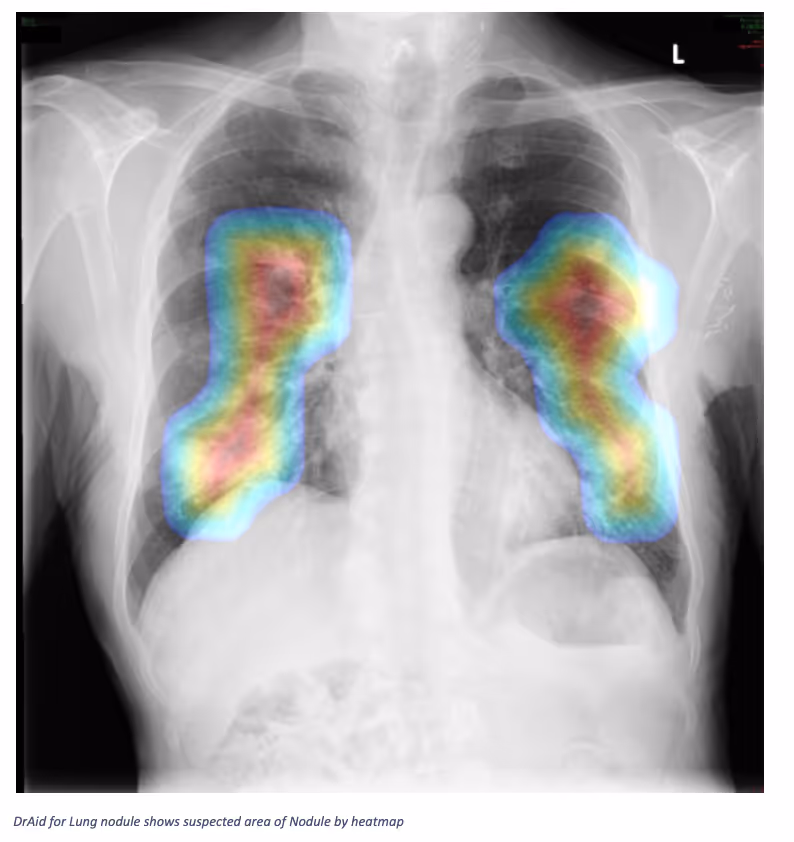

- Multiple lung nodules and masses in both lungs of variable size

ConclusionDrAid not only detected a nodule area but also highlighted more than 1 nodule area in both lungs.Interested in deploying DrAid at your health facility?Contact the Ferrum Health team to learn more.